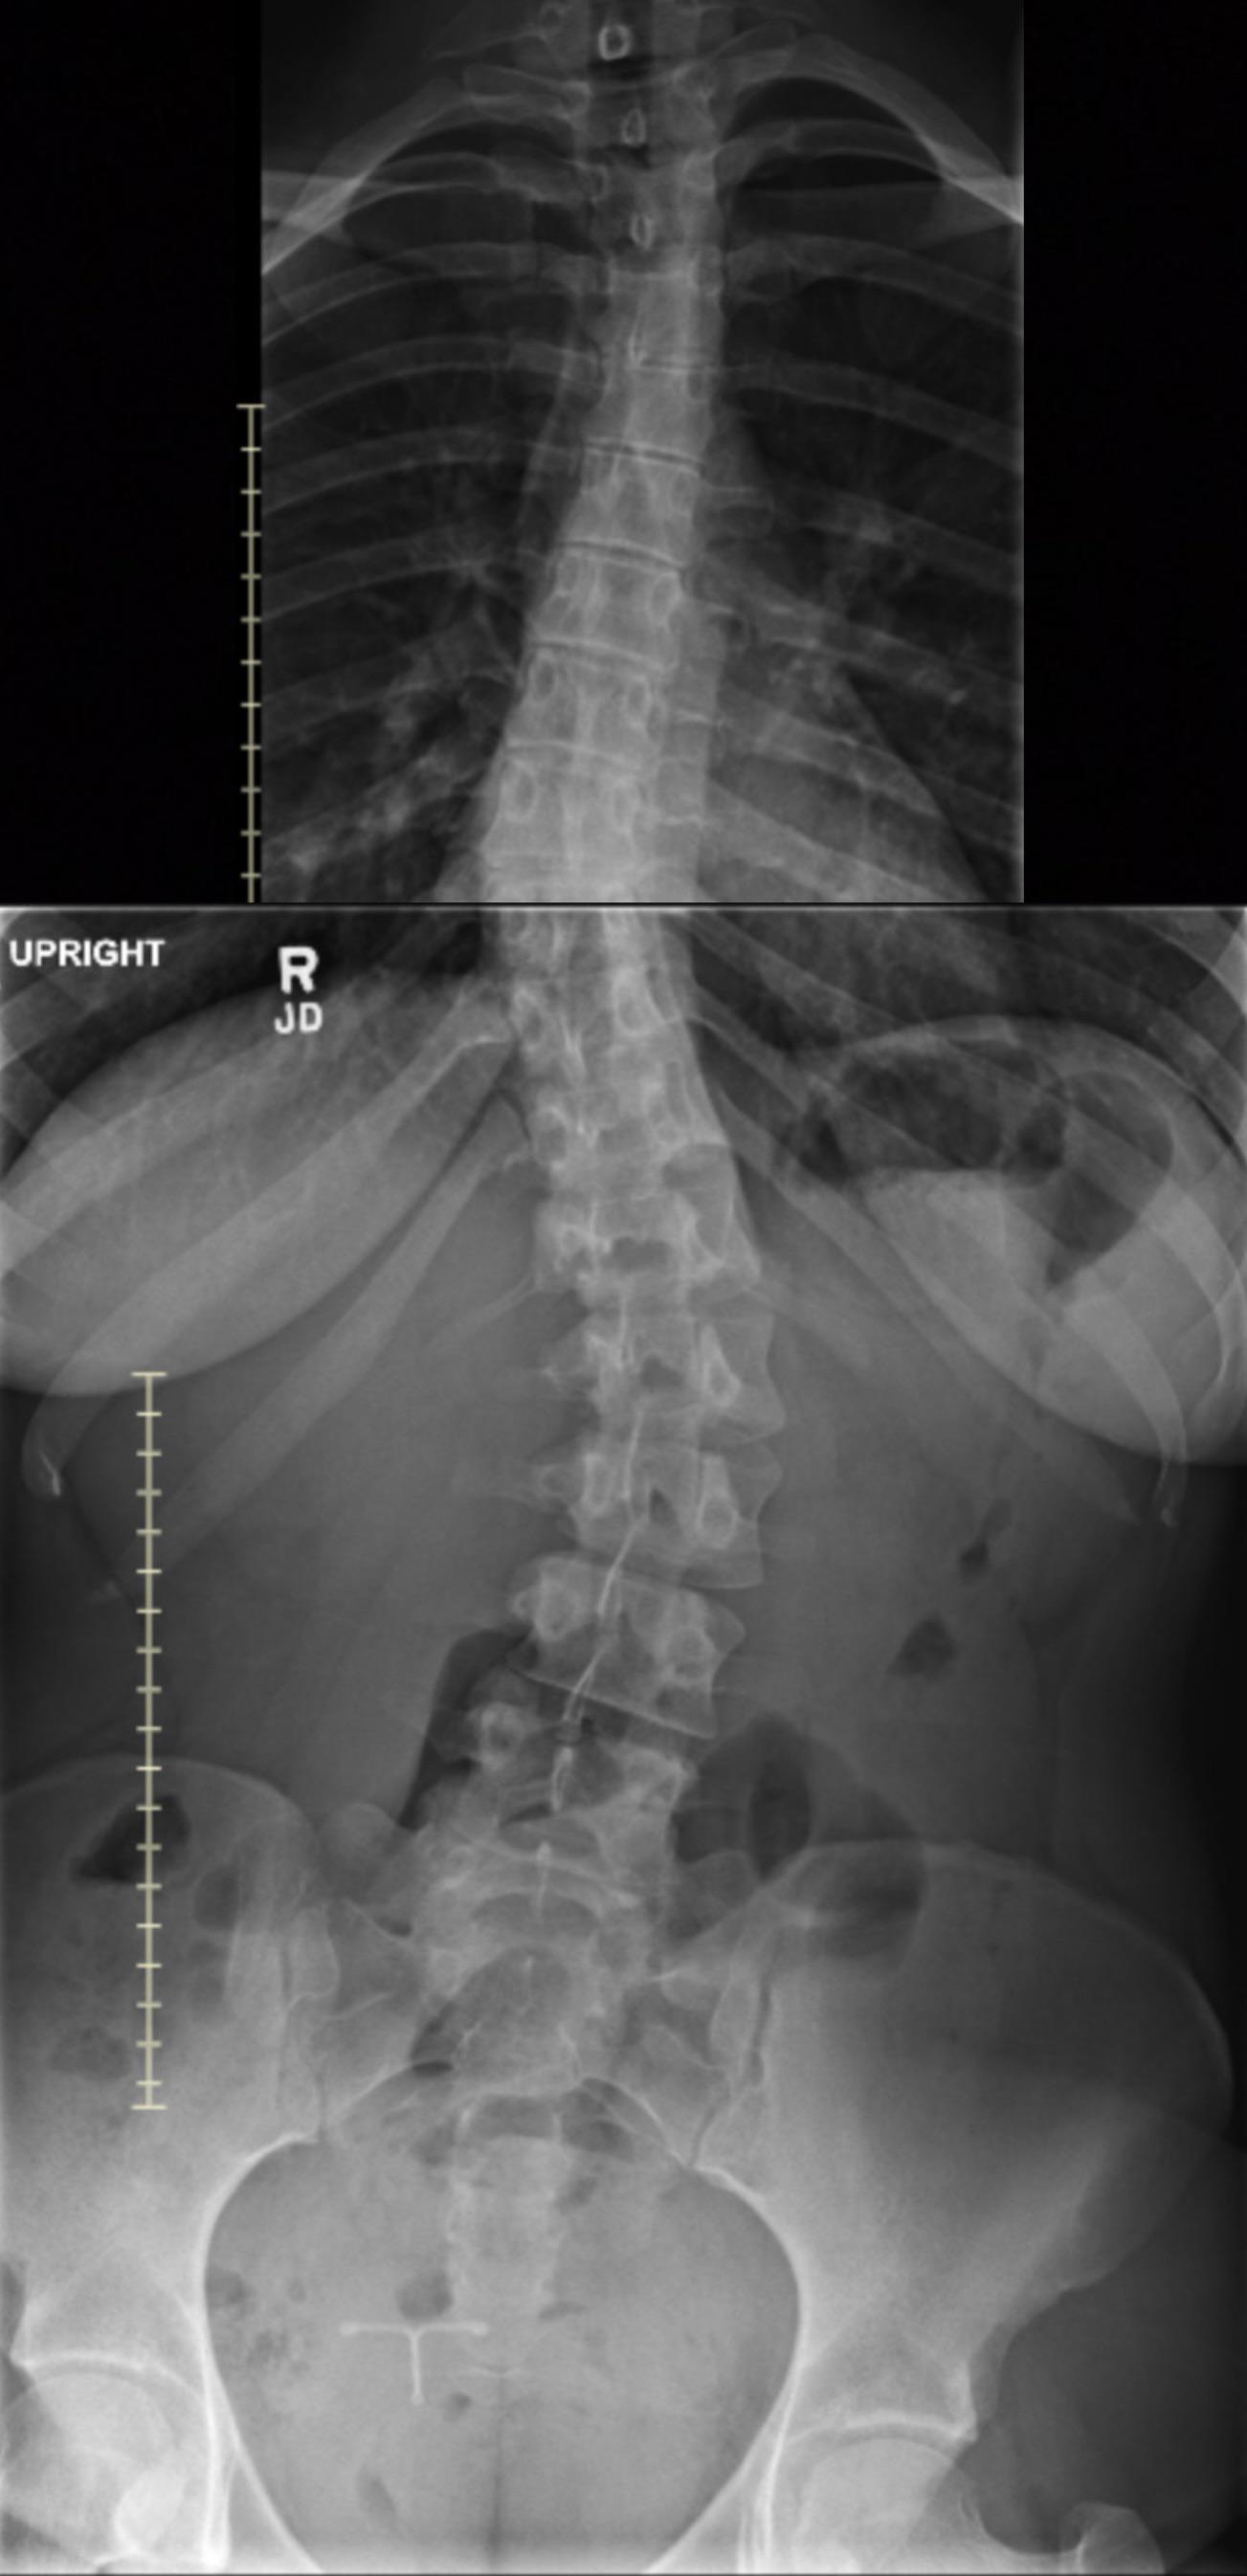

this is classified as mild because a severe scoliosis literally looks like they are folded on themselves

For anyone keen on x-rays, I changed positions slightly between them. Apologies if things aren’t lined up the best!

My spine looks similar to yours AFAIK. I have extra floating ribs and am (was?) 5 degrees short of any intervention.